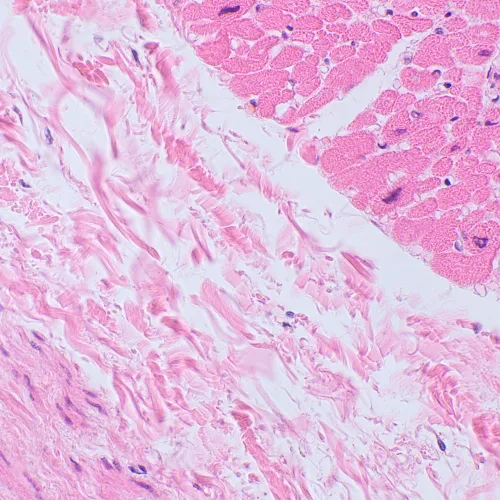

A MAGUS Bio 250TL mikroszkóppal biológiai minták vékony csiszolatait és keneteit lehet tanulmányozni. A megfigyelés áteső fényű világos látóterű mikroszkópos technikával történik. A fényforrás egy 3 wattos LED, az optika pedig végtelen síkú akromatikus objektívekből áll. A mikroszkóp támogatja a kiegészítő tartozékokat, köztük a sötét látóterű, a polarizációs és a fáziskontraszt eszközöket. A mikroszkóp ideális választás laboratóriumi elemzéshez, kutatásokhoz és oktatáshoz.